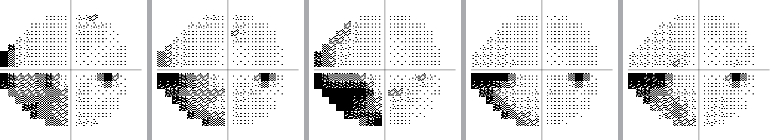

The visual field can be monitored over time to see if there is progression of glaucoma, or if the disease has stabilized as a result of treatment:

Example of a normal visual field over time

(The small dark spot is the eye’s "natural" blind spot.)

Example of a stabilized visual field over time

Example of progression of visual field loss over time